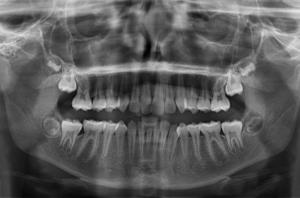

Si un traitement orthodontique est indiqué et que le moment est adéquat, nous allons réaliser un bilan orthodontique qui comprend :

• Des photographies du visage, du sourire et des arcades dentaires

• Des radiographies : Panoramique (pour une vision d’ensemble de la denture et de l’évolution dentaire), de profil (pour voir les relations et décalages entre les mâchoires) et si nécessaire du poignet (pour estimer le stade de croissance du patient et la croissance résiduelle disponible) et de face (pour mettre en évidence des asymétries)

• Des empreintes dentaires pour obtenir des moulages d’étude

À partir des éléments de ce bilan orthodontique, le praticien va pouvoir analyser les données cliniques, les photos, les radiographies pour une analyse céphalométrique et les moulages pour établir un diagnostic précis et proposer un traitement adapté.